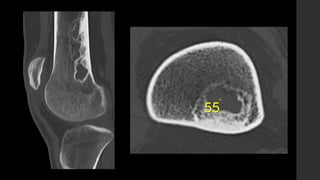

Fibroma no osificante.

• RX y CT

 Típicamente son circunscritos, asimétricos, lesiones radiolúcidas corticales con un anillo esclerótico.

 Frecuentemente son multiloculadas.

 Se localizan en la metáfisis, adyacente a la fisis.

 Cuando el paciente crece, parece que migra lejos del núcleo de crecimiento.

 No hay reacción perióstica asociada.

• IRM 

 Apariencia variable, depende de la etapa del desarrollo e involución de la lesión.

 Inicialmente la lesión muestra señal alta en T2 con anillo periférico con señal baja.

 Mientras madura la lesión muestra disminución de señal en todas las secuencias.

 Realce variable.

• MN 

 La apariencia depende, en el gamagrama, de la fase de la lesión.

 Generalmente es negativo, pero puede haber hiperemia leve con captación moderada durante la etapa de sanación.

Hetts SW, Hilchey SD, Wilson R et-al. Case 110: Nonossifying fibroma. Radiology. 2007;243 (1): 288-92.